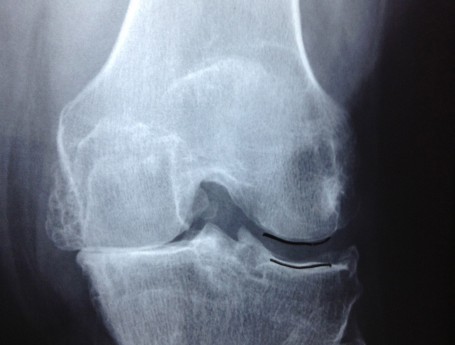

Revision Total Knee Replacement After Infection

• Revision Total Knee Replacement After Infection